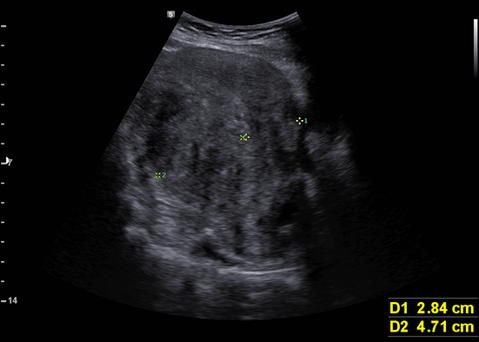

복부 초음파상 자궁근종/자궁선근증 관찰됨

; 평소 생리가 많은 날 외출하기 어렵고 패드가 흥건히 젖을 정도의 생리과다(menorrhagia)에 인한 반복되는 철결핍성 빈혈, 종괴 효과로 인한 방광 압박으로 소변 긴박 증상을 설명함.